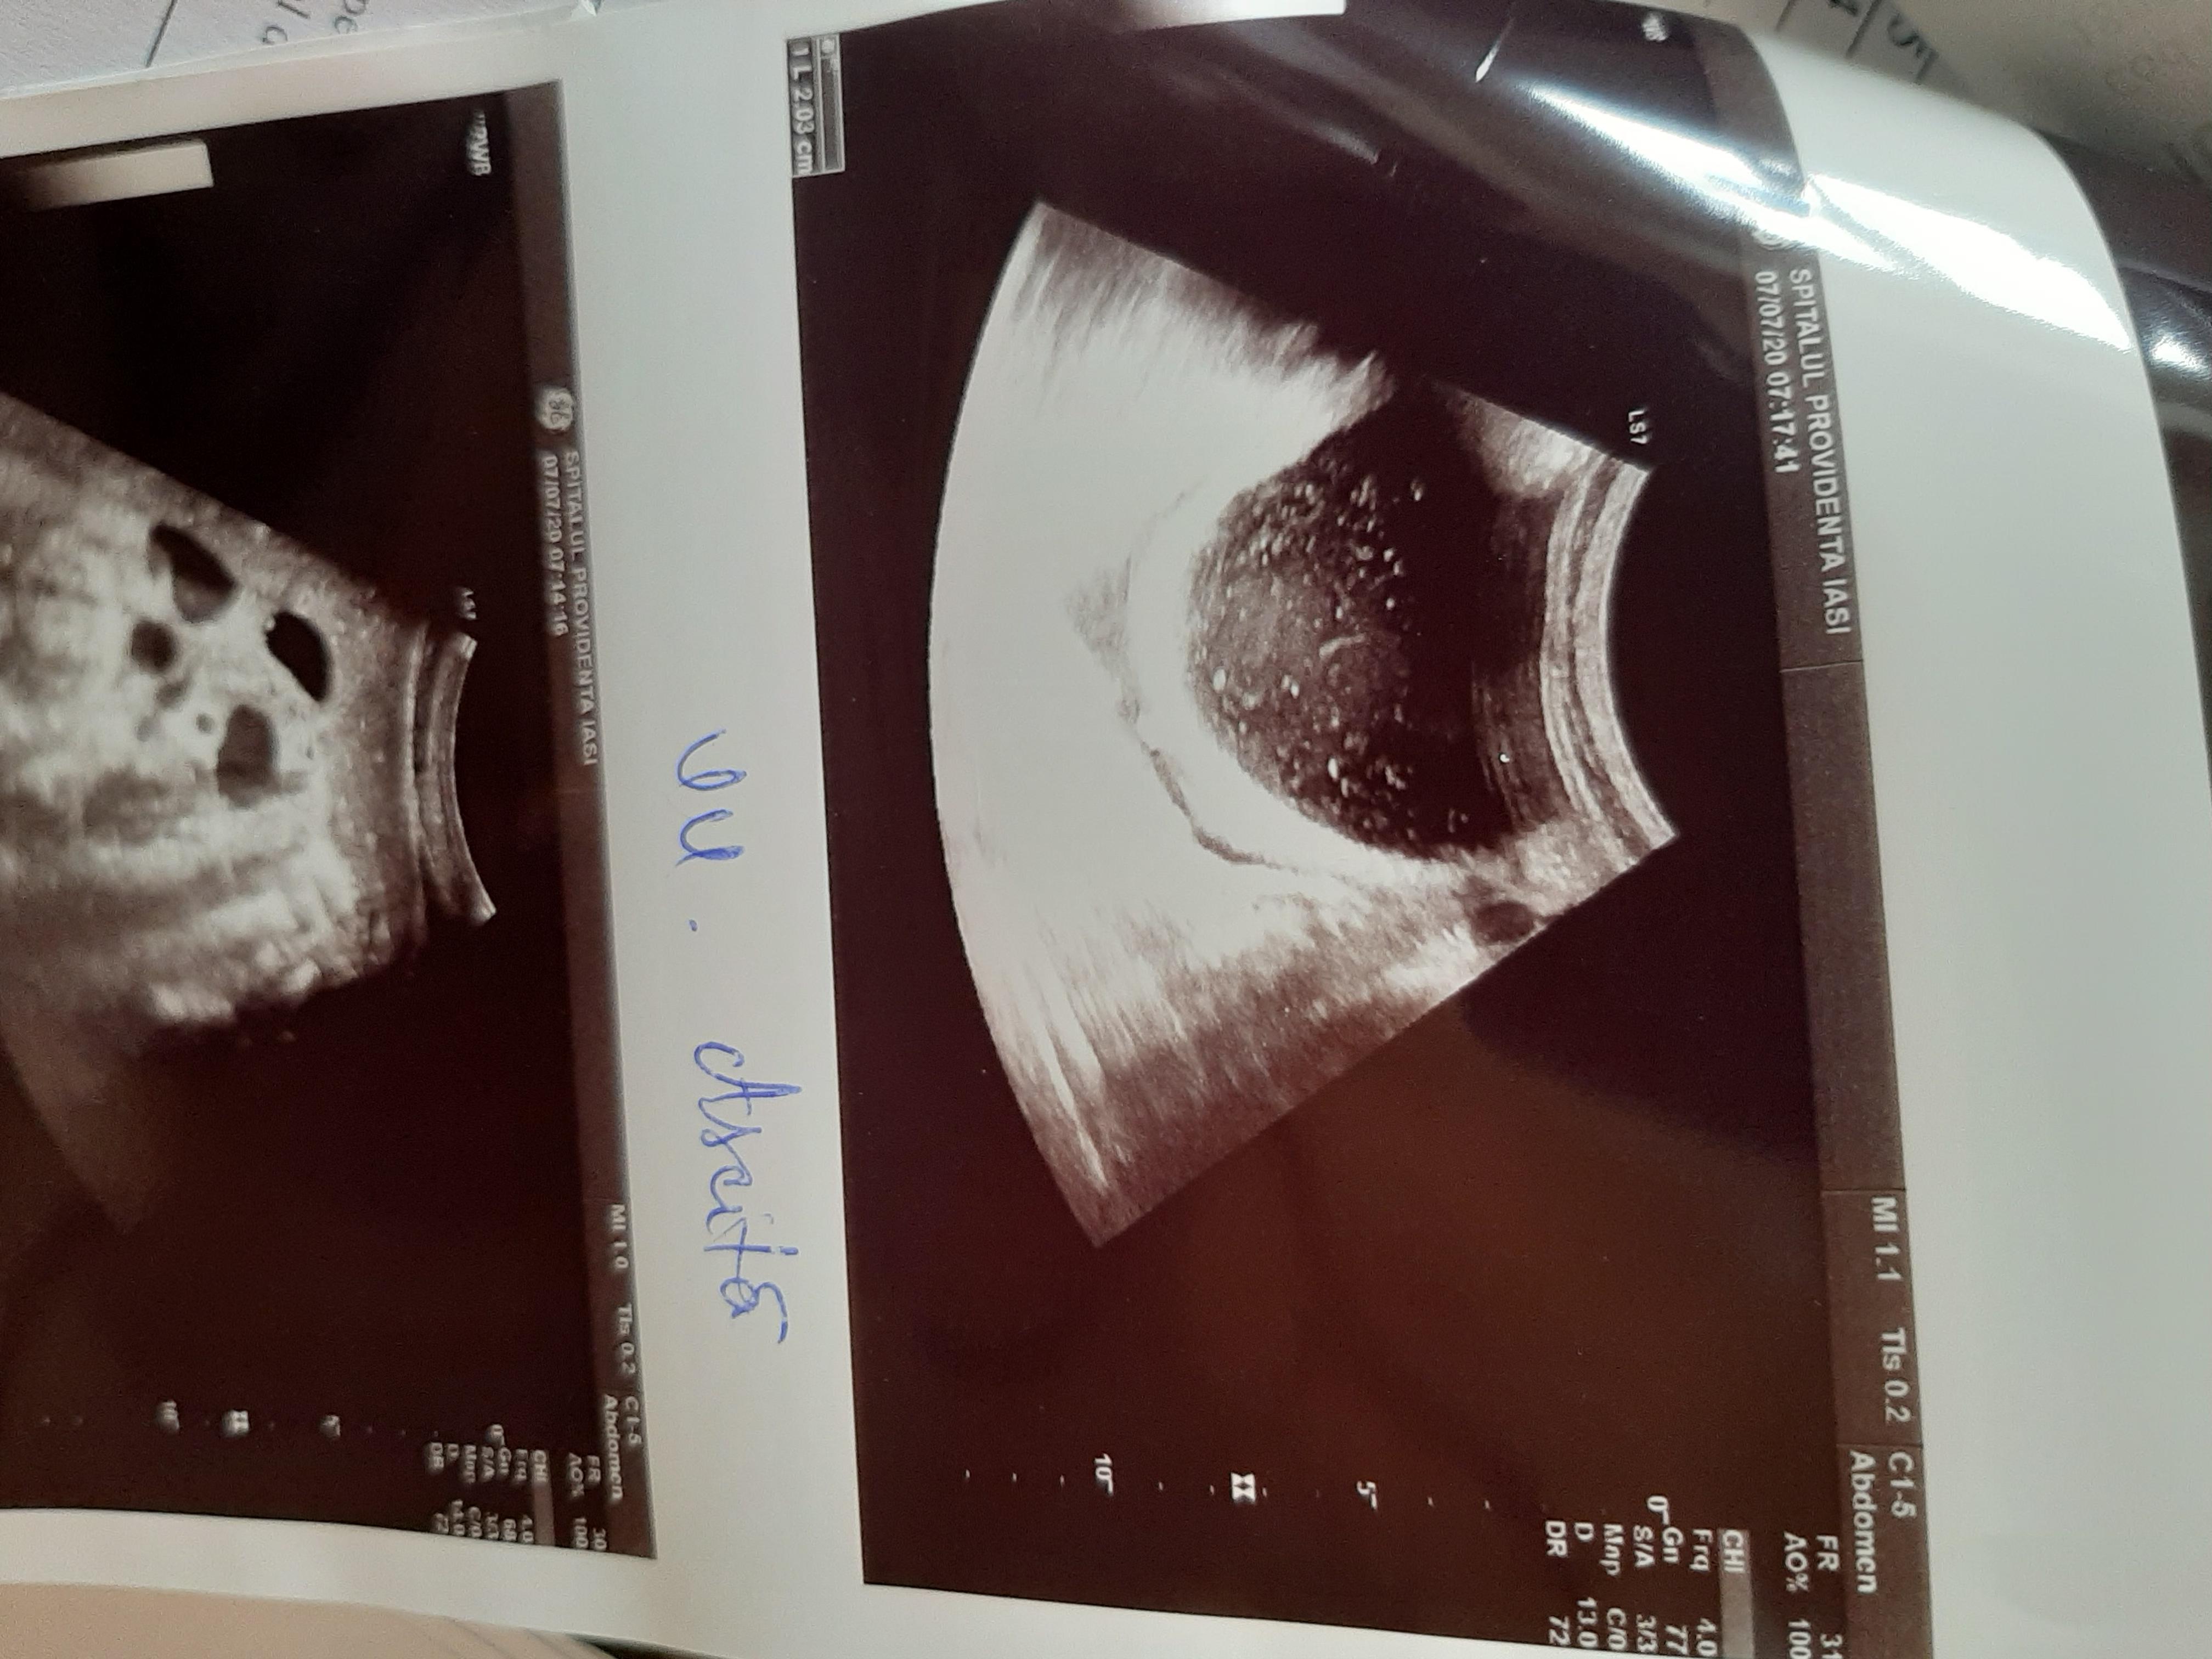

Diagnosticul medicilor a fost: sindrom hipoanabolic, litiază biliară veziculară, boală de reflux gastroesofagian, antecedente de colită repetată cu Clostridium Difficile.